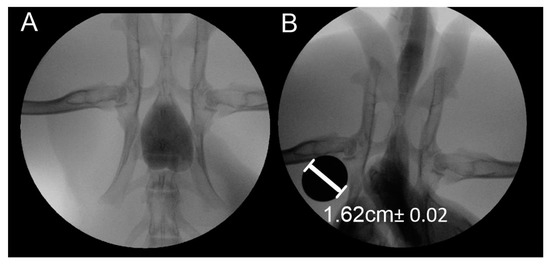

| Volume of Fluid [mL] | Diameter of the Urethra [mm] | Pressure Inside Urethra [kPa] |

| 20 | 4.19 Na | 1.5 ± 0.015 |

| 40 | 6.41 | 1.5 ± 0.015 |

| 60 | 7.54 | 1.5 ± 0.015 |

| 80 | 10.66 | 1.5 ± 0.015 |